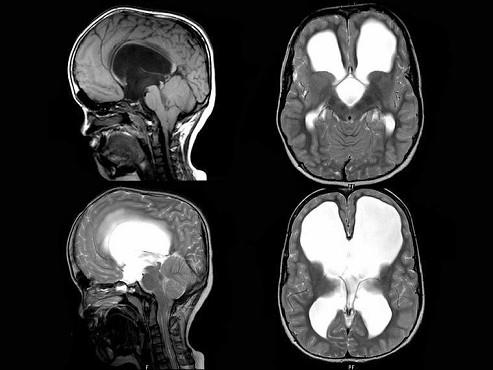

问题 女,10岁。头颅进行性异常增大,与身体不成比例。MRI检查如图,最可能的诊断为?(?)

选项 A.先天性中脑导水管狭窄 B.小脑扁桃体下疝 C.第四脑室中孔闭锁 D.第四脑室侧孔闭锁 E.先天性中脑导水管闭塞

答案 E